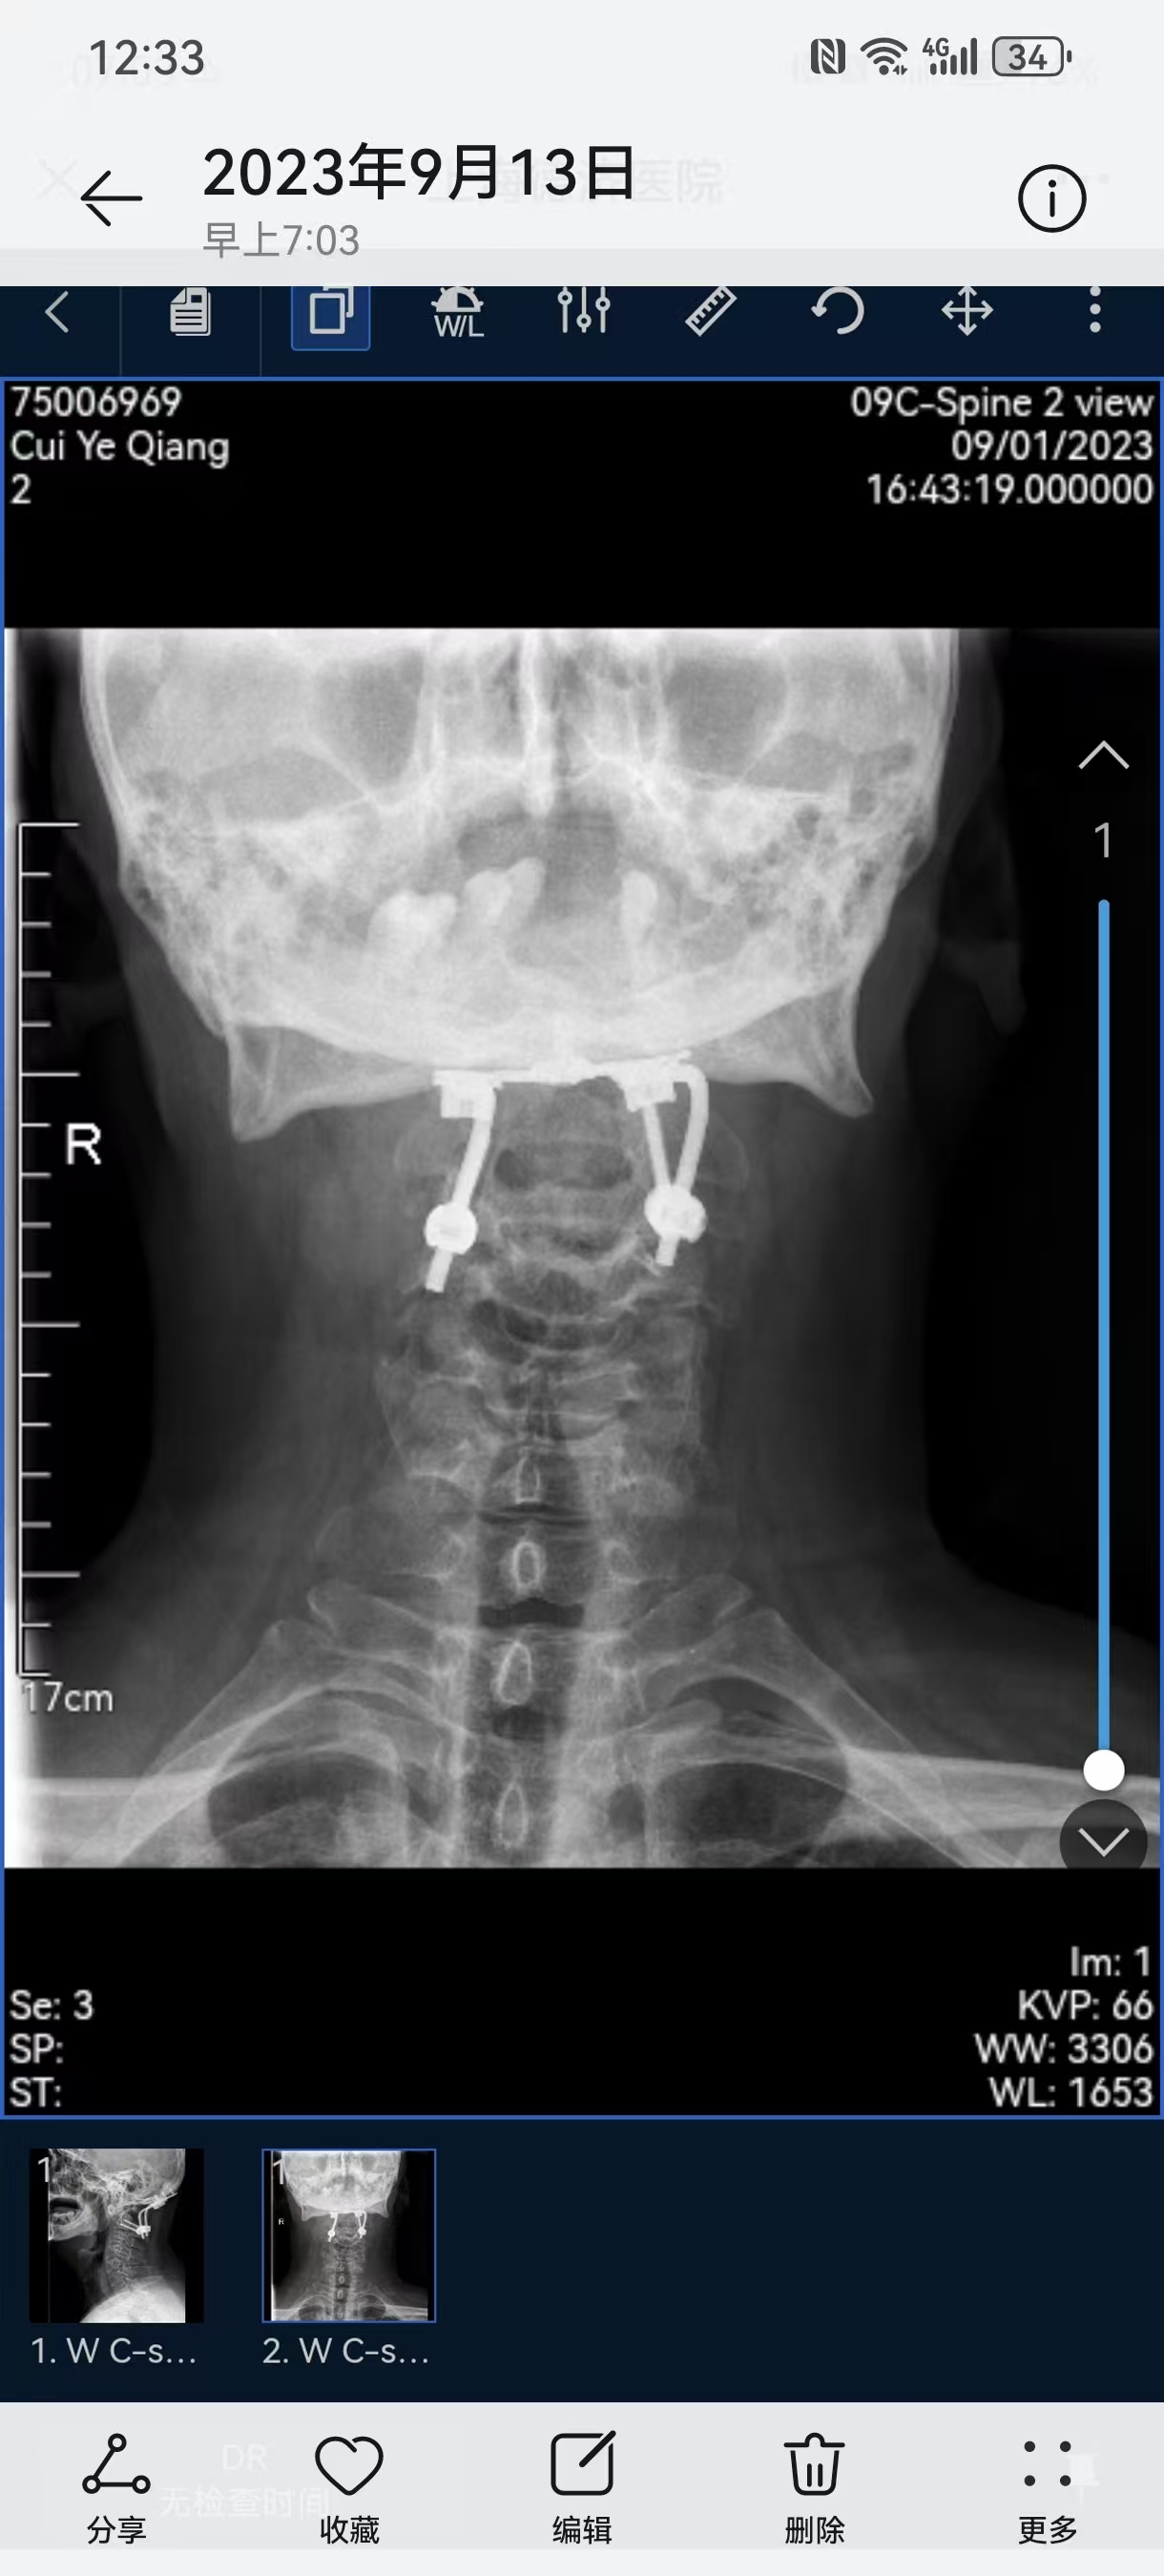

• 诊断:寰枢椎脱位,颅底凹陷

• 日期:2013

• 医院:上海长征医院

• 主刀:史建刚

• 日期:2021